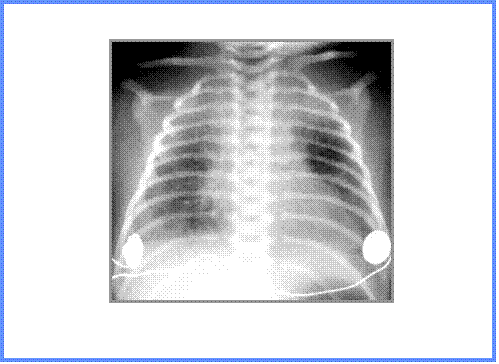

Strep pneumonia in newborn

© R3